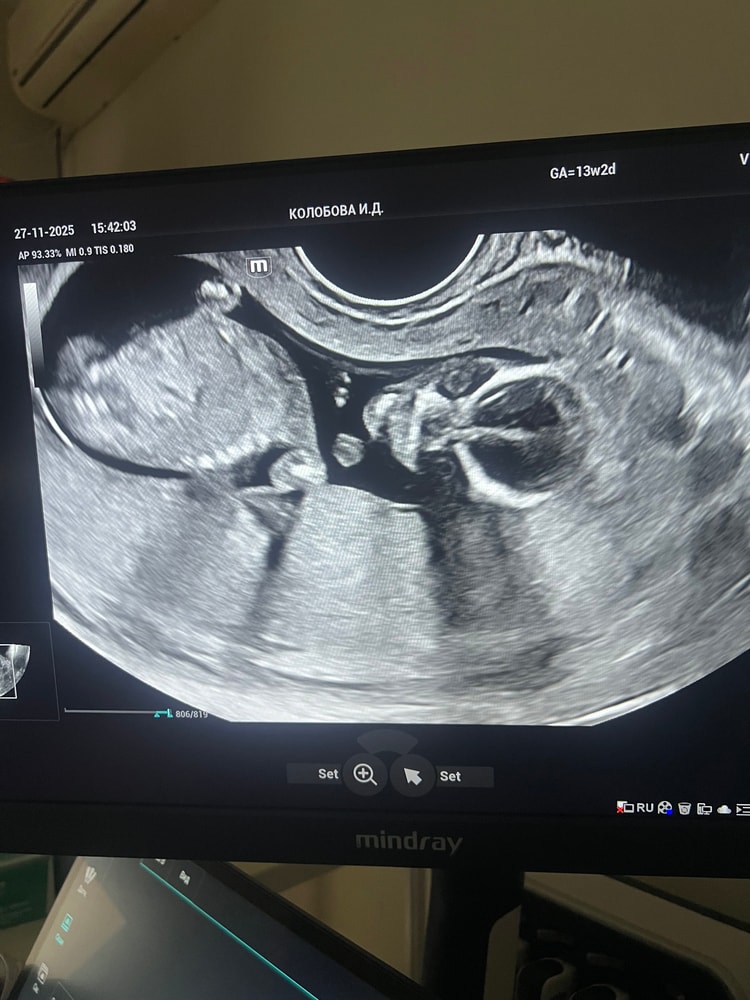

По узи все супер, врач узи была в этот раз просто солнышко, все показала, фоточку сделать разрешила даже в 3д малыша показала) жду рисков по крови, но там должно быть все ок, сданный нипт дарит уверенность) такой вот смешной парень внутри, даже зрачки видно)